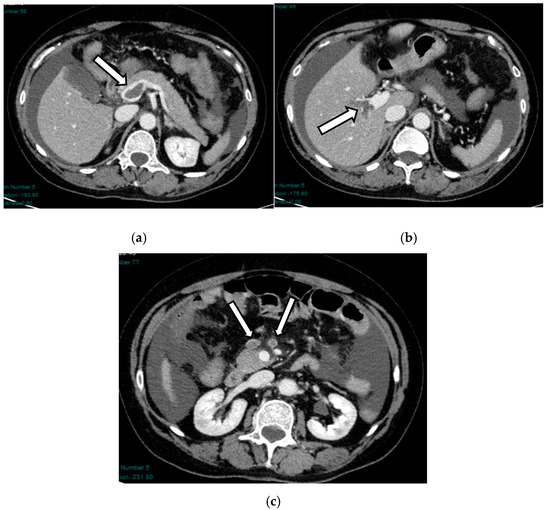

Acute mesenteric ischemia (AMI) is a clinical condition caused by vascular insufficiency, resulting in intestinal damage. Is often underestimated, if not driven by clinical suspicion, due to the non-specific clinical symptoms (usually represented by acute abdominal pain) and the absence of reliable markers, which results in a poor prognosis and high mortality. We can identify three main forms of AMI: arterial, venous, and non-occlusive. Arterial AMI is the most frequent form, caused by occlusion of the superior mesenteric artery or one of its branches. Venous AMI is the least frequent, caused by thrombosis of the superior mesenteric vein or its branches. Non-occlusive AMI is due to a state of hypovolemia, which is frequent in patients who have undergone surgery. Given the difficulty of diagnosis based on the clinic alone, the radiologist plays a central role in identifying radiological signs of intestinal ischemia and in avoiding misdiagnosis. The radiologist’s role is mainly to identify factors predictive of necrosis, which allow us to stratify patients and direct them towards the proper management. The aim of this review is to provide indications for an adequate CT protocol, including an unenhanced phase, an arterial phase, and a venous phase, as well as to underline the features to investigate in the different forms of AMI, in order to increase the diagnostic capacity in this challenging disease. Full article

Figure 1